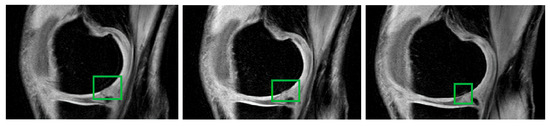

Novel Hybrid Optimized Clustering Schemes with Genetic Algorithm and PSO for Segmentation and Classification of Articular Cartilage Loss from MR Images

by Jan Kubicek, Alice Varysova, Martin Cerny, Jiri Skandera, David Oczka, Martin Augustynek and Marek Penhaker

Mathematics 2023, 11(4), 1027; https://doi.org/10.3390/math11041027 - 17 Feb 2023

Cited by 4 | Viewed by 2424

Abstract

Medical image segmentation plays an indispensable role in the identification of articular cartilage, tibial and femoral bones from magnetic resonance imaging (MRI). There are various image segmentation strategies that can be used to identify the knee structures of interest. Among the most popular [...] Read more.

Medical image segmentation plays an indispensable role in the identification of articular cartilage, tibial and femoral bones from magnetic resonance imaging (MRI). There are various image segmentation strategies that can be used to identify the knee structures of interest. Among the most popular are the methods based on non-hierarchical clustering, including the algorithms K-means and fuzzy C-means (FCM). Although these algorithms have been used in many studies for regional image segmentation, they have two essential drawbacks that limit their performance and accuracy of segmentation. Firstly, they rely on a precise selection of initial centroids, which is usually conducted randomly, and secondly, these algorithms are sensitive enough to image noise and artifacts, which may deteriorate the segmentation performance. Based on such limitations, we propose, in this study, two novel alternative metaheuristic hybrid schemes: non-hierarchical clustering, driven by a genetic algorithm, and Particle Swarm Optimization (PSO) with fitness function, which utilizes Kapur’s entropy and statistical variance. The goal of these optimization elements is to find the optimal distribution of centroids for the knee MR image segmentation model. As a part of this study, we provide comprehensive testing of the robustness of these novel segmentation algorithms upon the image noise generators. This includes Gaussian, Speckle, and impulsive Salt and Pepper noise with dynamic noise to objectively report the robustness of the proposed segmentation strategies in contrast with conventional K-means and FCM. This study reveals practical applications of the proposed algorithms for articular cartilage extraction and the consequent classification performance of early osteoarthritis based on segmentation models and convolutional neural networks (CNN). Here, we provide a comparative analysis of GoogLeNet and ResNet 18 with various hyperparameter settings, where we achieved 99.92% accuracy for the best classification configuration for early cartilage loss recognition. Full article

Show Figures

Figure 1